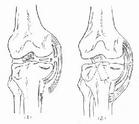

膝關節內翻應力試驗的結果判定:當伸直位試驗陰性屈曲30°位陽性者,表示膝關節LCL斷裂合併外側關節囊韌帶的後1/3、弓形韌帶、膕肌腱損傷;當伸直位和屈曲30°位均為陽性者,表示膝LCL斷裂同時合併十字韌帶斷裂;當伸直位陽性,屈曲30°位陰性者,表示單純膝LCL斷裂或鬆弛。

(1)外側側搬試驗:外側副韌帶損傷後做內翻側搬試驗,可以發現外側張力下降和鬆弛。I度損傷,外側無明顯鬆弛;II度損傷外側鬆弛但有抵抗感;III度損傷,外側鬆弛無抵抗感。試驗應在伸直位和屈膝30º位檢查,與健側對比。

(2)外側間隙開口感:外側副韌帶損傷後除I度損傷外,均有外側間隙開口感。檢查也應在伸直和屈膝30º位進行,與健側對比。